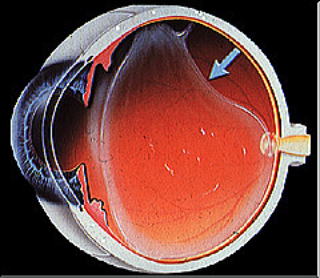

망막 박리란 망막이 안구의 내벽으로부터 분리되는 상태를 말합니다. 이는 망막이 안구의 기저층에서 분리되어 시세포의 영양 공급이 미비해지며, 결과적으로 시력 저하를 유발할 수 있는 심각한 안과 질환입니다.

- 열공성 망막 박리 : 가장 일반적인 형태로, 망막에 구멍이 생기면서 유리체의 액체가 이 구멍을 통해 들어가 망막을 들어 올리는 상황입니다. 대개 외상이나 고도근시 등으로 인해 발생합니다.

- 견인성 망막 박리 : 당뇨병성 망막병증이나 기타 망막 질환에 의해 흉터 조직이 형성되고, 이 조직이 망막을 당겨 들뜨게 만드는 것으로 발생합니다. 특히 유아기 또는 청소년에서 많이 발생할 수 있습니다.

- 삼출성 망막 박리 : 종양이나 염증 등에 의해 망막 아래에 체액이 쌓여 망막이 떨어지는 경우입니다. 이 상태는 망막 자체의 구멍이나 찢어짐 없이 발생할 수 있습니다.